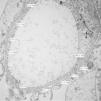

Of the 38 patients with TBMD, the vast majority were women (81.57%) and only 7 (18.42%) were men. The age range was from 6 to 66 years, with a mean of 29 years, being more common in the second decade of life (23.68%). The findings on clinical presentation, glomerular lesions overloaded with the pattern of GBM structural changes, degree of interstitial fibrosis and associated tubular atrophy and degree of arteriolopathy are shown in Table 2. In the histopathological study, it was observed that in the majority of cases (42.10%) the glomeruli were within the normal limits. Some segments of glomerular basement membranes with “thinning” appearance were observed alternating with dilated capillary loops (Fig. 2), some with erythrocytes in their lumens and pigmented cylinders in the tubules. There was focal widening of the mesangial matrix with mild proliferation in only 6 cases (15.78%). As in AS, the direct immunofluorescence study did not have specific deposits in any of the cases. However, routine immunoreactants are performed to rule out other pathologies that have the same clinical presentation, such as IgA nephropathy. Finally, the most important findings to define the TBMD were found in TEM, on average the GBMs measured 170.63nm (Fig. 3), with an average minimum measurement of 92.52nm and an average maximum measurement of 272.84nm.